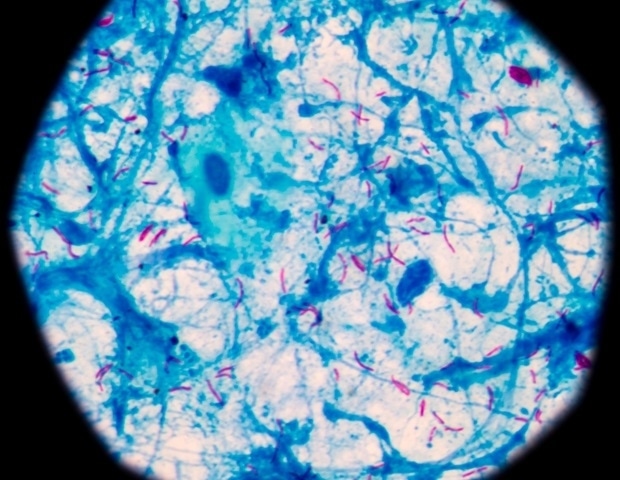

Mycobacterium tuberculosis, החיידק הגורם לשחפת (TB), נבדל מרוב החיידקים ביכולתו להדביק אנשים בשקט במשך חודשים ואף שנים לפני שהם מתעוררים